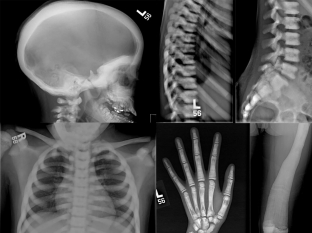

Although symptoms usually appear in early childhood, the disease can be detected at any age. Sometimes hardening of the bone canal is an incidental finding on x-ray.

With the progression of marble disease, patients come to the doctor with complaints of pain and fatigue in the limbs when walking. Fractures often occur with marble disease, especially of the femur. Bone fusion occurs at a normal time, but the likelihood of developing osteomyelitis is increased. To clarify the diagnosis, an X-ray examination of flat and tubular bones is carried out, which reveals a sharp compaction of the bone tissue.